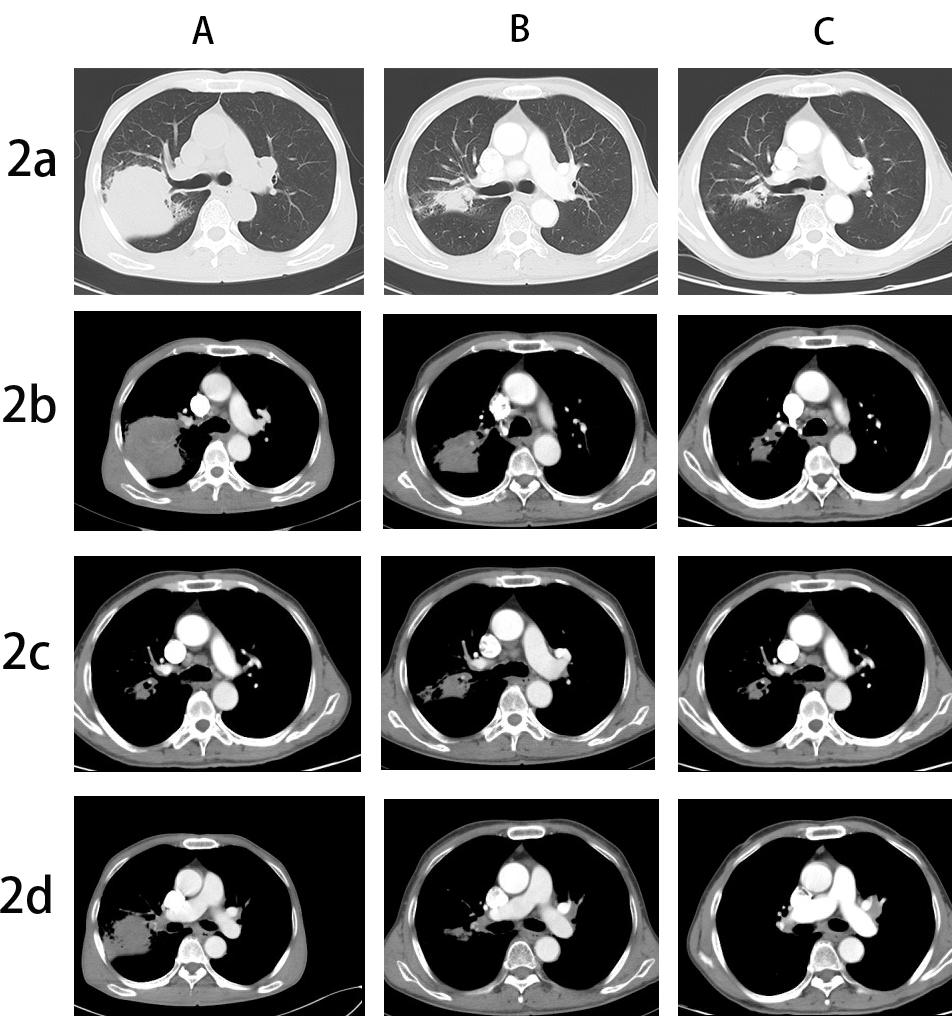

A 67-year-old male, with a continuous smoking history of over 30 years, was admitted to hospital for blood in phlegm half a month and was diagnosed as right lung upper lobe adenocarcinoma with right hilar and mediastinal lymph node metastasis examined by PET-CT. CT-guide needle biopsy was performed, and subsequent HE staining and immunohistochemistry confirmed adenocarcinoma with PD-L1(+,5%). Quantitative polymerase chain reaction (qPCR) assay of 10 genes in primary tumor tissue showed G12S\G12D mutation in exon 2 of KRAS gene. Neoadjuvant chemotherapy is administered to patients anticipated to benefit from subsequent adjuvant chemotherapy; however, it only modestly enhances 5-year recurrence-free and OS rates by about 5% to 6% [7]. The incorporation of immune checkpoint inhibitors (ICIs) into neoadjuvant chemotherapy demonstrates potential, having a minimal impact on the likelihood of significant perioperative complications or mortality, while presenting new opportunities for managing treatable NSCLC, with a major pathological response rate varying between 21% and 45%. Additionally, induction with ICIs does not increase toxicities that could delay surgical interventions [8]. Following the results of the CheckMate-816 study, immunochemotherapy is now suggested as a neoadjuvant approach [9]. After discussing in the multidisciplinary team (MDT), in view of the difficulty of operation, three cycles of neoadjuvant Camrelizumab(anti-PD-1 antibody) combined with pemetrexed and carboplatin were administered to the patient. However, repeat imaging after two cycles demonstrated concern for disease progression with right mediastinal lymph node increased and new left hilar and mediastinal(4L) lymph node metastasis. But the right upper lung lesions became significantly smaller with the tumor biomarker, CEA, NSE and Cyfra21-1 continued to decline (Figure 1). However, the side effects of immunochemothrapy are small, with no high-grade toxicities, the patient chose to continue to receive one more cycle treatment. Repeat imaging after one more cycle treatment demonstrated that decreasing of the primary lesion but stable right mediastinal and left hilar and mediastinal lymph node (Figure 2a-d). Positron emission tomography-computed tomography (PET-CT) was performed and showed that the local residual tumor with slightly high FDG metabolism, hilar and mediastinal lymph node enlargement with high FDG metabolism (Figure 3A-D). After the re-MDT, it was considered that the tumor shrank significantly and the tumor markers continued to decrease. The nature of the contralateral hilar lymph nodes was the same as that of the 4L group lymph nodes. It is recommended to complete the EBUS-tbna examination and puncture the 4L group lymph nodes. Lymph node biopsy of group 4L lymph node by Ebus-tbna showed no cancer tissue was found. In view of the possibility of pseudoprogression, after a sufficient communication, the patient underwent a right lung upper lobectomy and hilar and mediastinum lymph node dissection. Surgical pathology showed there was no residual cancer tissue, which achieved pathological complete remission, and the enlarged lymph nodes including 4L were presented as change after immunotherapy, no visible tumor cells existed. Now, the patient had finished all treatment and reexamination periodically for 13 months, no evidence of relapse or metastasis exist.